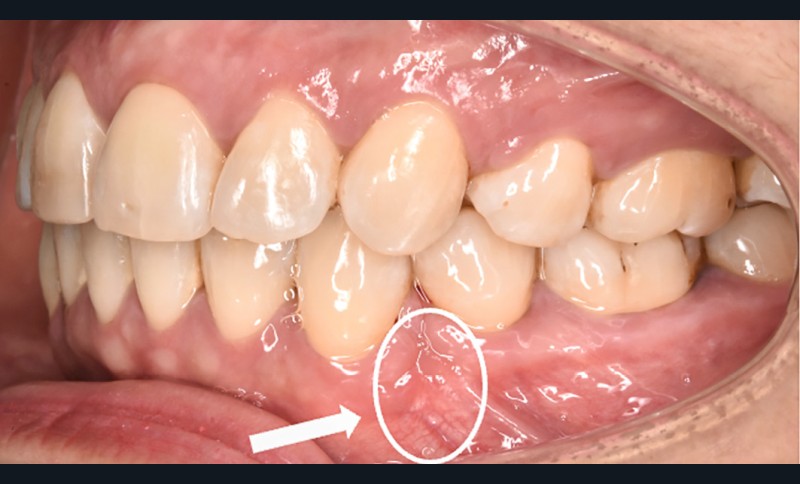

Des avulsions sont réalisées dans 15 % des traitements d’orthodontie [1], principalement en cas d’encombrement sévère ou de vestibuloversion incisive marquée. Les fentes gingivales sont des défauts parodontaux fréquemment observés lors de la fermeture orthodontique d’un espace d’avulsion (dans 35 à 100 % des cas selon les auteurs [2-7]) (fig. 1).

La fente est définie comme une invagination linéaire du tissu interdentaire en direction mésiale ou distale avec une profondeur de sondage d’au moins 1 [2] ou 2 mm [3]. Elle se présente sous forme d’un pli (ou fissure) de gencive plus ou moins sévère pouvant cacher un défaut osseux sous-jacent.